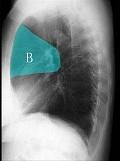

如图所示正常胸部X线影像图像上,该英文字母所代表的肺段为 ( )A.尖段B.后段C.尖后段D.舌叶上段E.前段

问题 如图所示正常胸部X线影像图像上,该英文字母所代表的肺段为 ( )

选项 A.尖段 B.后段 C.尖后段 D.舌叶上段 E.前段

答案 E